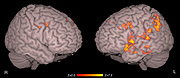

身体醜形障害患者の脳スキャン

自分を醜いと思い込む身体醜形障害を持つ人の中には,容姿を気にするあまり整形手術を繰り返したり,自殺を考える人もいるという。この病気にはどうやら生物学的な根拠があるらしく,一見正常な患者の脳に,ちょっとした欠陥があることがわかった。UCLAの研究班が,患者と健常者に鮮明度の異なる3種類の顔写真を見せ,脳の機能をMRIで分析したところ,健常者では鮮明度の低い写真の全体像を右脳で処理していたのに対し,患者では左脳で処理していることがわかった。つまり,身体醜形障害を持つ人は,細かい部分がわからないと,それを補足して分析しようとする傾向にあるようだ。(吉田素子)

Although they look normal, people suffering from body dysmorphic disorder(1), or BDD, perceive(2) themselves as ugly(3) and disfigured(4). New imaging research(5) reveals(6) that the brains of these people look normal but function(7) abnormally(8) when processing(9) visual details.

Reported in the December edition(10) of the journal Archives(11) of General Psychiatry(12), the UCLA findings(13) are the first to demonstrate(14) a biological reason(15) for patients' distorted(16) body image(17).